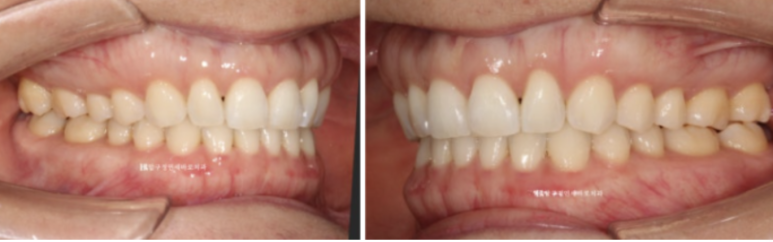

23.07-24.05

미니스크류를 심고 치료하면 인비절라인 라이트로 가능한 케이스였습니다.

23.7

11개월간 치료 후 끝났습니다.

23.07~24.05